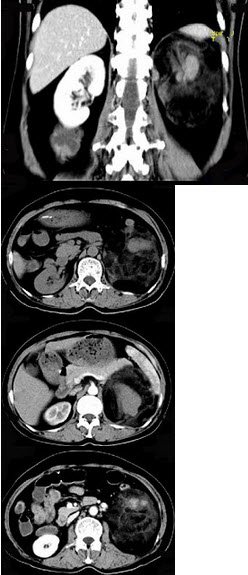

女,64岁,左侧腰部胀痛,行CT扫描,下列说法正确的是( )

A:左肾区可见一巨大的占位性病灶,境界较清楚,胰腺尾部受压向前推移

B:该病灶密度不均匀,其内可见脂肪密度影,且呈不均匀强化

C:考虑为左肾来源的血管平滑肌脂肪瘤

D:考虑为左侧肾上腺来源的髓样脂肪瘤

E:考虑为腹膜后来源的脂肪肉瘤